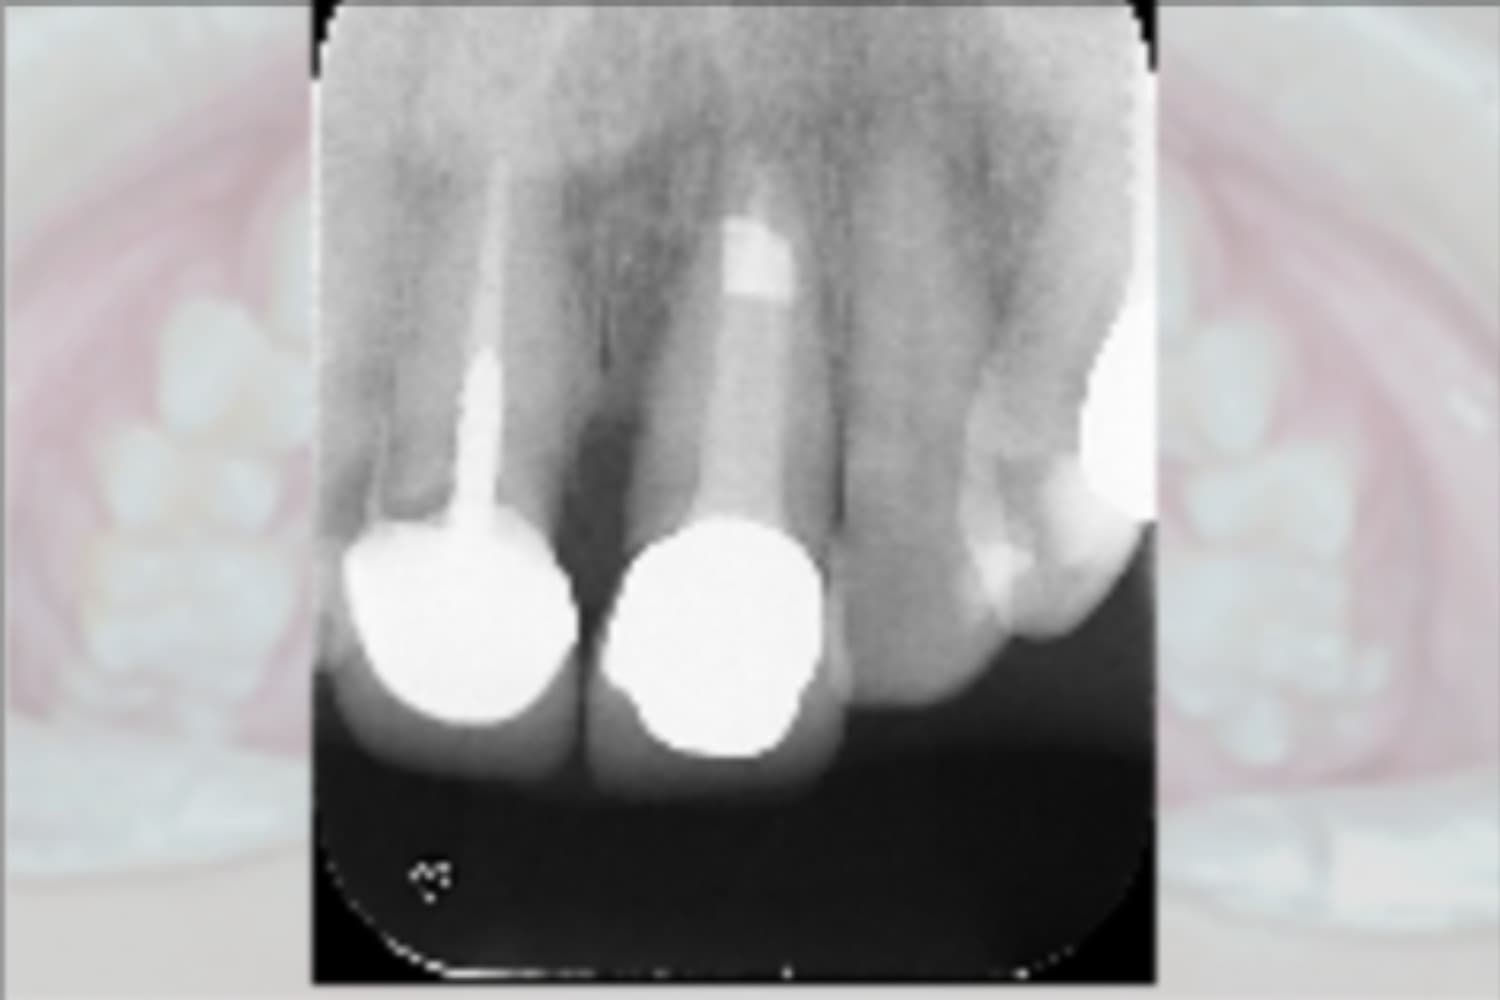

左上前歯のインプラント治療

Before

After

左上前歯を抜歯しインプラント治療を行なった

主訴

上の前歯の歯茎の腫れ

治療期間

8カ月

治療回数

8回

費用

533,500 円

副作用・リスク

・複合処置(抜歯・インプラント・骨造成)を一度に行ったことで感染リスクが高くなりました。また、結合不良が起こるリスクも高くなりました。